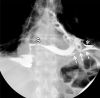

An esophagopericardial fistula is a rare complication of esophageal malignancy, trauma, or surgery. Imaging is a cornerstone of diagnosis, with detection of pneumopericardium or hydropneumopericardium at imaging raising suspicion for pyopneumopericardium and prompting immediate search for the causative pathologic process. Given the high associated mortality rate of over 50% for patients with esophagopericardial fistulas, early diagnosis and intervention are vital. Supplemental material is available for this article. © RSNA, 2020.